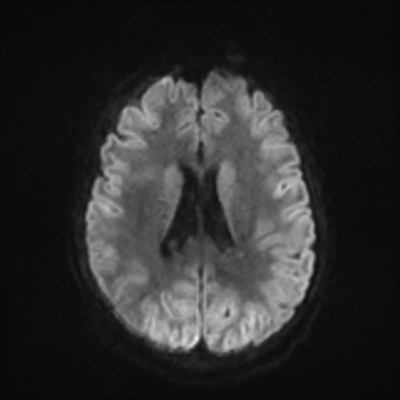

MRI brain (DWI)

You can clearly see diffuse cortical and basal ganglia diffusion restriction, and that of his deep cerebellar nuclei as well. The right occipital lobe abnormalities are a little more prominent, but then you remember that he is known to have had a right occipital stroke weeks ago.

In reviewing his data, you know that he doesn't have any of the strong predictors of a poor neurologic prognosis. However, based on these findings on MRI, along with the absent reactivity on cEEG, you are able to tell the primary team and the patient's family that he is likely to have a poor prognosis, based on these multiple moderate predictors. Recovery is not completely impossible-- there is more uncertainty with this prognostication than if we were able to get SSEPs-- but you're very worried about his outlook and that any potential recovery would require a very protracted rehabilitation period. Given his high cervical cord injury level, tracheostomy would be required anyway. So, it comes down to whether his family thinks he'd want to pursue these aggressive measures.